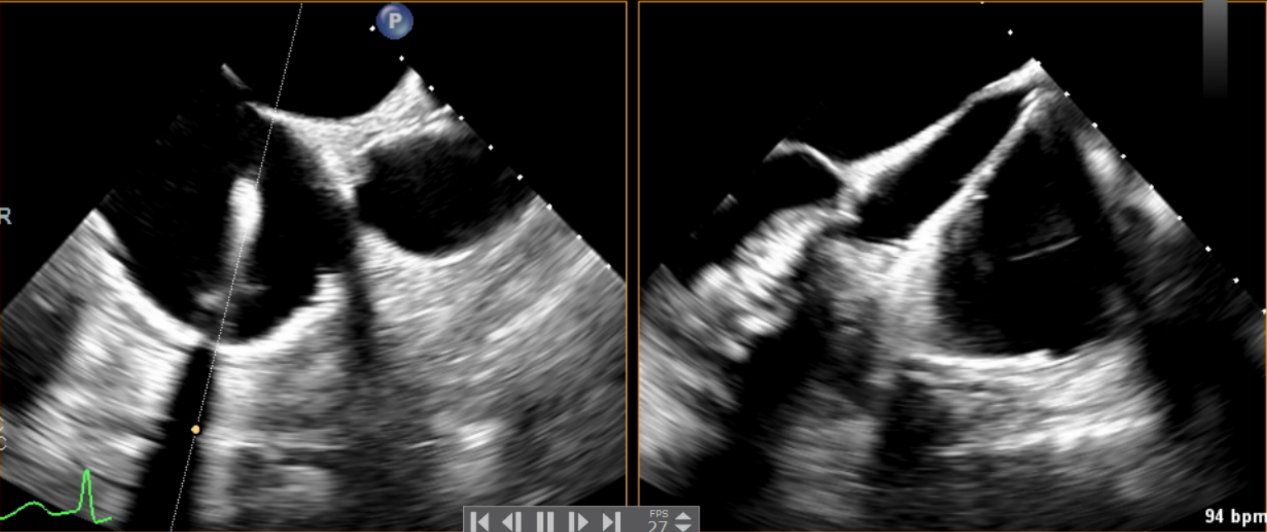

術前超聲提示大量三尖瓣反流

術中輸送器在超聲引導下調整位置

術后超聲提示無瓣周漏